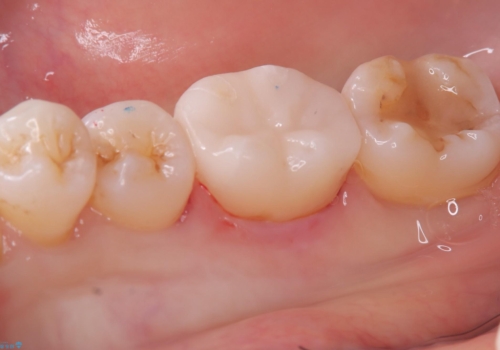

コンタクトの再現と歯冠色補綴物へのやり替えを目的とし、セラミックインレーでの治療となりました。

メタルインレーを歯冠色のものに変えたいという希望もあったため、セラミックインレーでのやり替えによるコンタクトの再現をしています。

セラミックインレーセット時ラバーダム防湿を行っています。